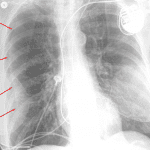

Age: 68

Sex: Female

Indication: Chest pain, dyspnea

Findings

- No focal airspace disease or edema

- Skin fold overlies the right hemithorax. No pneumothorax

- No pleural effusion

- Emphysema

- Aortic atherosclerosis

- Left subclavian approach cardiac rhythm maintenance device with right atrial and right ventricular leads

- Bilateral partially calcified breast prostheses

Diagnosis

- Skin fold

No evidence of acute cardiopulmonary disease. Skin fold overlies the right hemithorax without evidence of pneumothorax.

Emphysema.